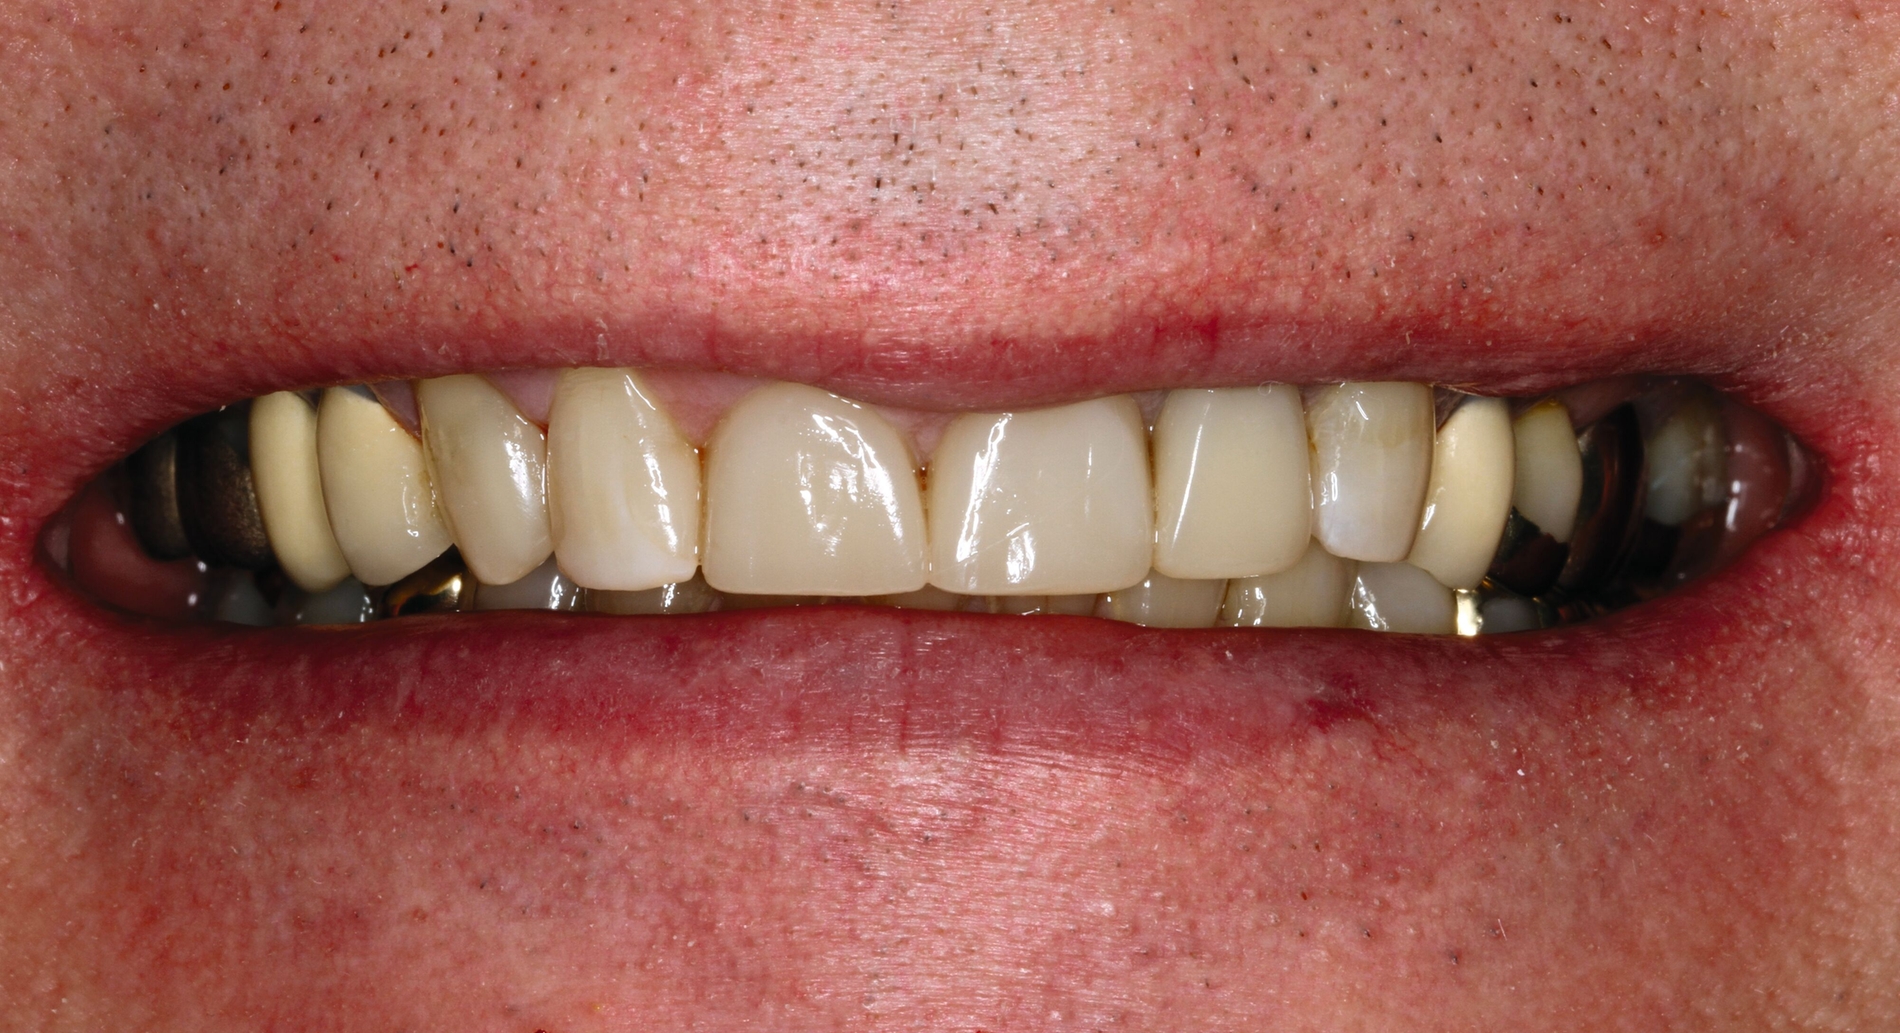

Nach Beendigung der restaurativen Therapie (Abbildungen 11 und 12) wurde dem Patienten zur Schonung der Zahnhartsubstanz und der Restaurationen vor Parafunktionen eine adjustierte Oberkiefer-Aufbissschiene für die Nacht angefertigt. Es wurde ein konsequentes Recall-Programm (nach drei, sechs, neun und zwölf Monaten, danach halbjährlich) realisiert, um die Restaurationen, die Erosionsanamnese sowie die häusliche Mundhygiene zu kontrollieren. Nach zwanzig Monaten Beobachtungszeitraum zeigen sich suffiziente Restaurationen (Abbildung 13). Der Patient ist mit der Ästhetik und der Funktion sehr zufrieden, sein Wohlbefinden hat sich gegenüber dem Ausgangszustand deutlich gesteigert.